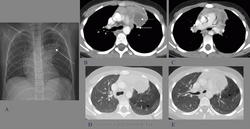

Добавочный трахеальный бронх.

Трахеальный бронх, который может быть истинно добавочным или смещенным, относится к числу редких пороков развития бронхо-лёгочной системы

Аномалии ветвлений бронхиального дерева весьма многочисленны. В большинстве случаев они не приводят к каким-либо выраженным проявлениям заболевания и, как правило, выявляются только при профилактическом обследовании. В комбинации, нарушая нормальный процесс аэрации и мукоцилиарного очищения, аномалии ветвлений создают предпосылки для наслоения инфекции и формирования хронических воспалительных заболеваний легких. Помимо этого, аномалии бронхиальных ветвлений нередко сочетаются с другими пороками развития легких, имеющими характерные проявления.

Среди аномалий бронхиальных ветвлений чаще всего встречается трахеальный бронх. Выделяют различные варианты трахеального бронха: добавочный, смещение верхнедолевого бронха или его ветвей на трахею. В большинстве случаев трахеальный бронх отходит от правой стенки трахеи. Считается, что в зоне, вентилируемой трахеальным бронхом, могут формироваться бронхоэктазы, нагноительные процессы, эмфизема. Наслоение инфекции приводит к формированию необратимых структурных деформаций бронхов, бронхоэктазии.

Добавочный трахеальный бронх.

Из архива AFIP

Из архива AFIP

Из архива AFIP